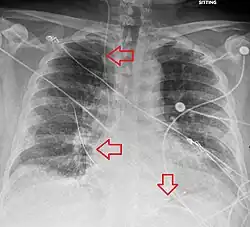

Pós-procedimento

Uma radiografia após o procedimento é obtida para confirmar a colocação do eletrodo de estimulação e descartar complicações como pneumotórax [2][3]. A desfibrilação e a cardioversão ainda podem ser realizadas em alguém com marcapasso temporário[2].

Complicações

As complicações incluem disritmias cardíacas e aquelas relacioniadas à colocação de um cateter venoso central, como o pneumotórax [3].